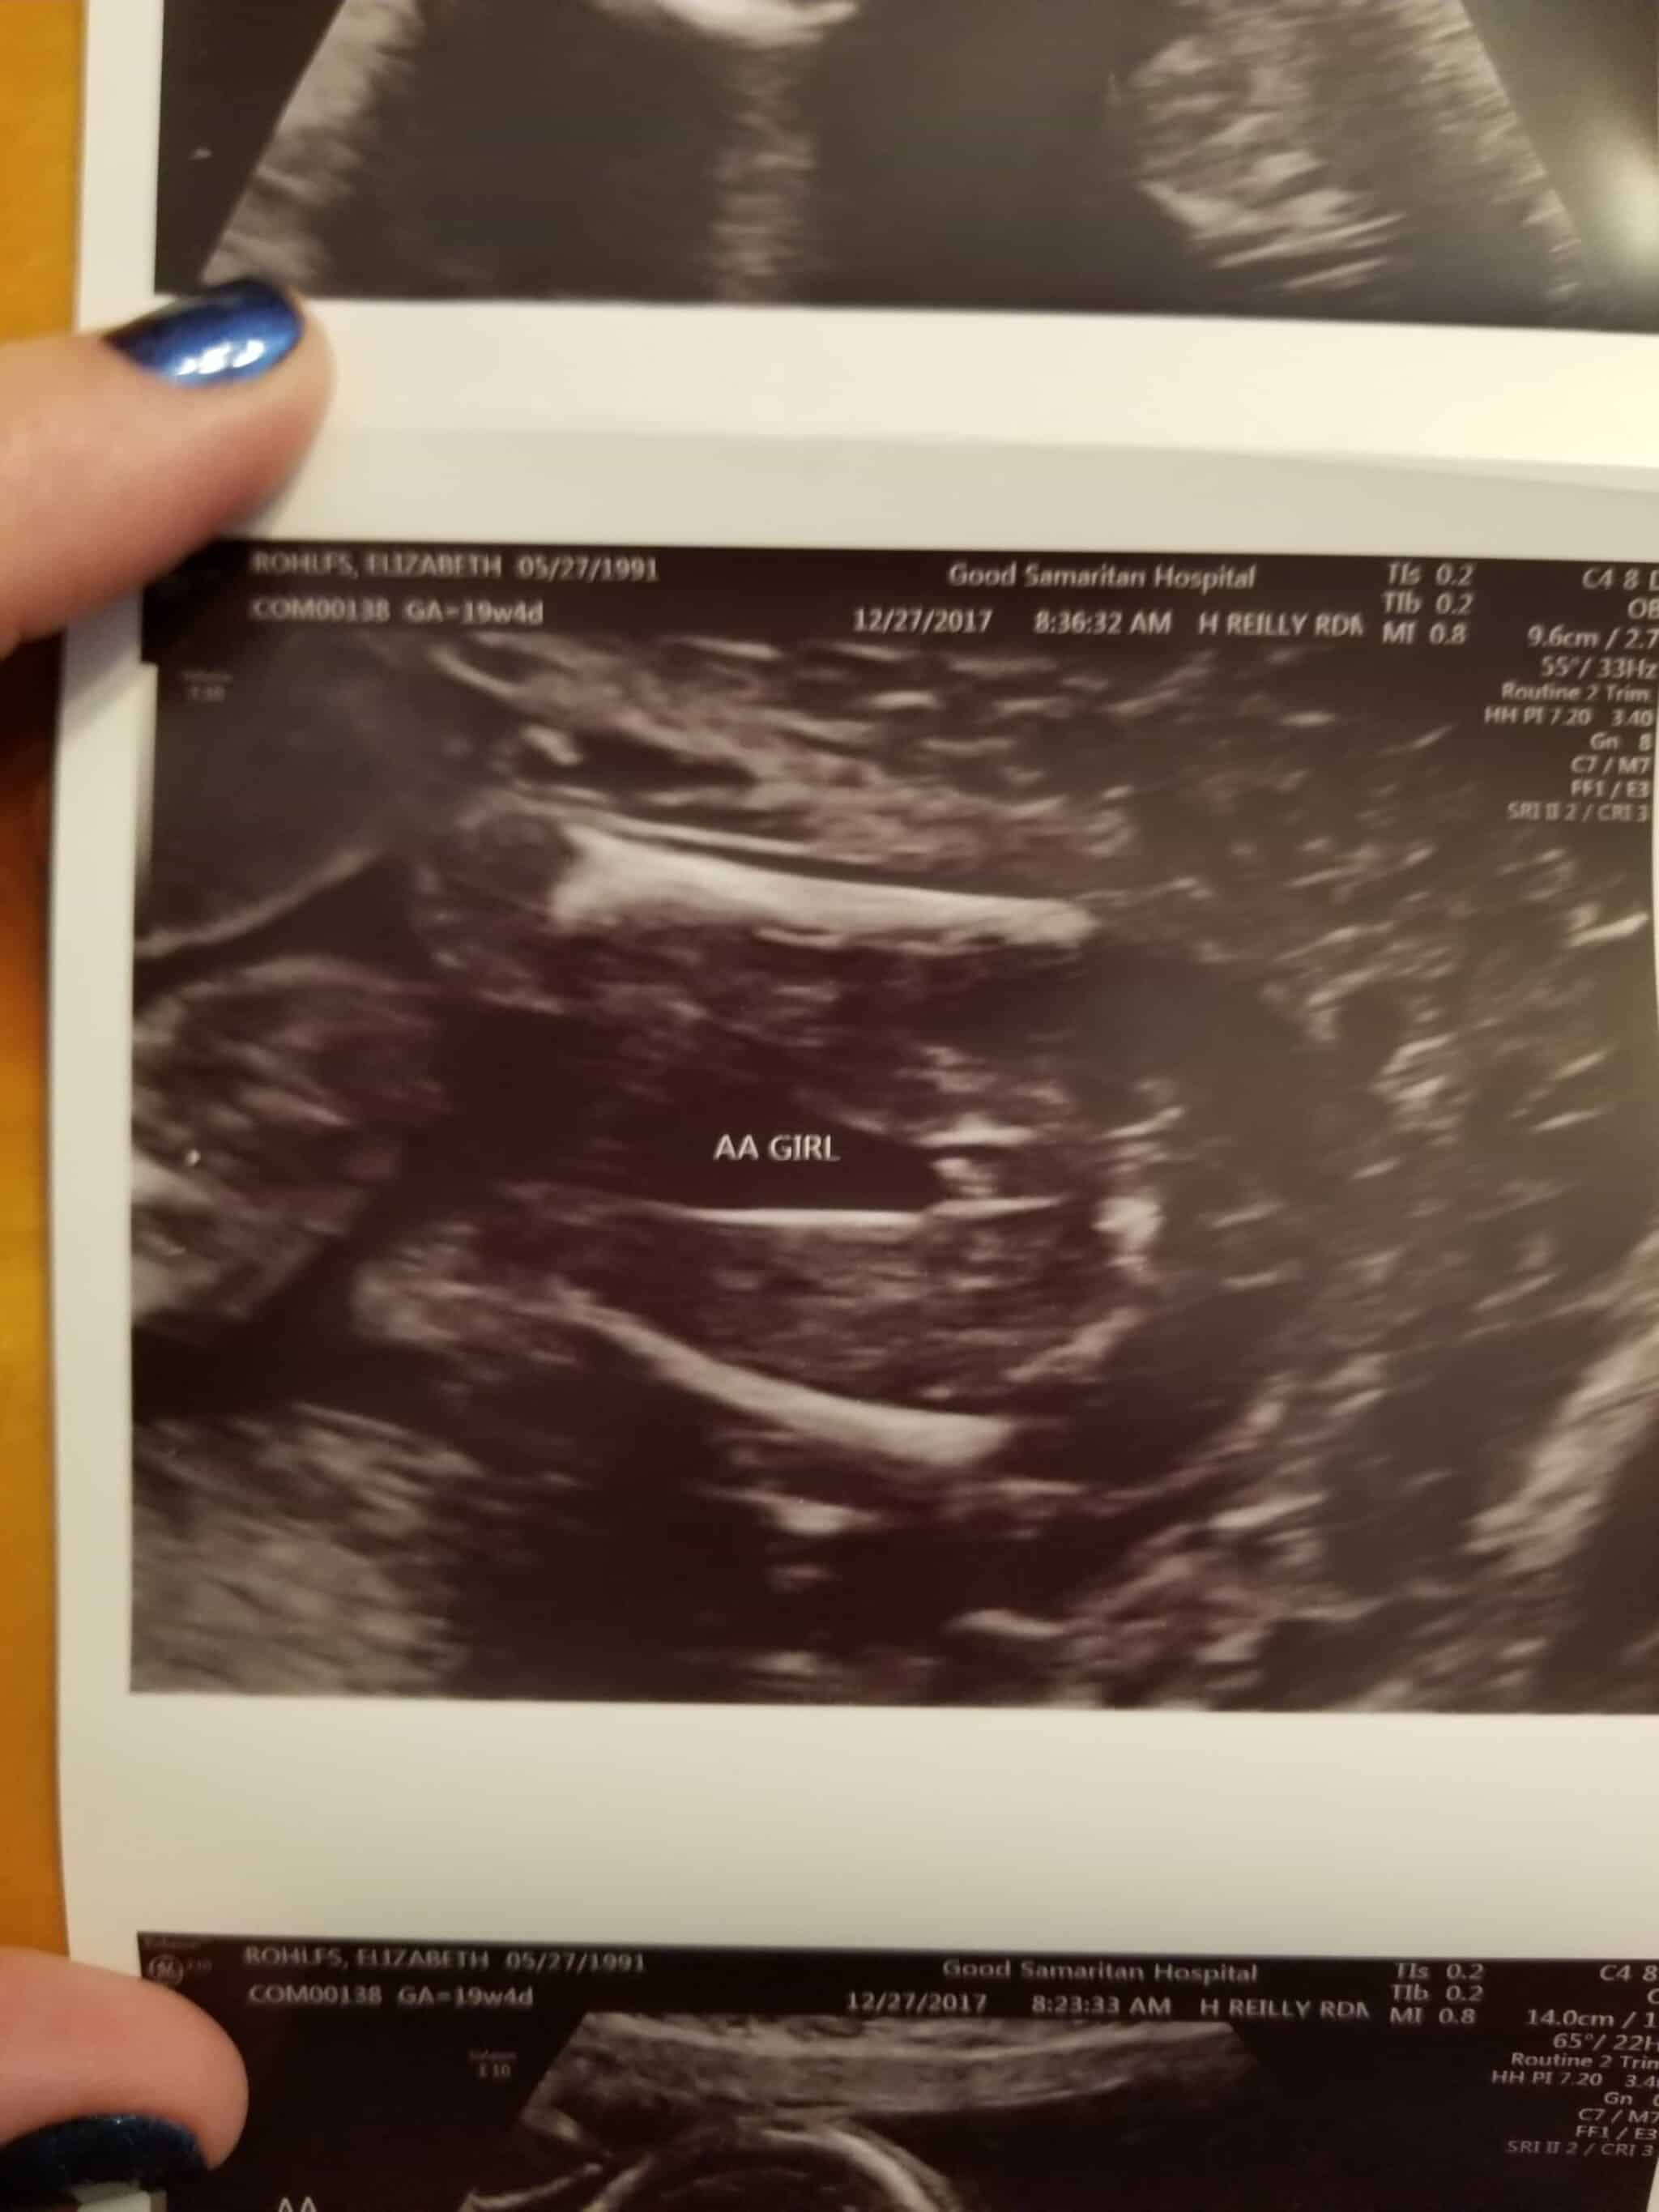

Ultrasound Photos at 19 Weeks Pregnant With Twins